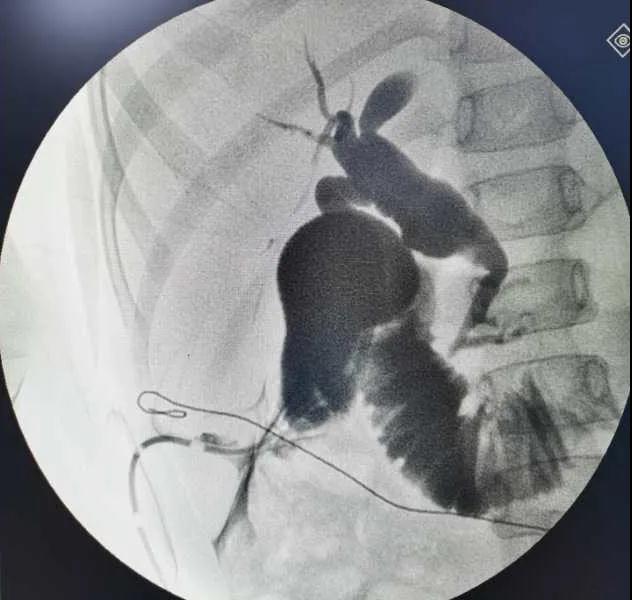

5月7日,西安國際醫(yī)學(xué)中心醫(yī)院小兒外科郭正團教授團隊成功為1名膽總管囊腫患兒進行了腹腔鏡膽管造影 腹腔鏡膽總管囊腫切除 腹腔鏡肝管空腸吻合術(shù)。目前,患兒恢復(fù)良好,已正常進食。

入院后,謝崇醫(yī)生積極為患兒完善術(shù)前準(zhǔn)備,MRCP(核磁共振膽道水成像)顯示該患兒為膽總管囊腫Ic型,有明顯的胰膽合流異常。面對復(fù)雜的病情,小兒外科郭正團主任立即組織團隊進行術(shù)前討論,制定了完善的手術(shù)方案及應(yīng)急措施。

5月7日,一切準(zhǔn)備就緒,郭正團主任主刀,帶領(lǐng)小兒外科團隊進行腹腔鏡膽管造影 腹腔鏡膽總管囊腫切除 腹腔鏡肝管空腸吻合術(shù)。術(shù)中,患兒膽總管與周圍肝動脈及門靜脈粘連嚴(yán)重,給手術(shù)增加了難度。郭正團主任沉著冷靜,操作嫻熟,完整剝離了膽總管囊腫及遠端胰腺段膽管,肝總管與空腸完成了Roux-en-Y吻合,手術(shù)進行順利。術(shù)后第2天,玲玲就可以下床活動;第6天,已正常飲食。